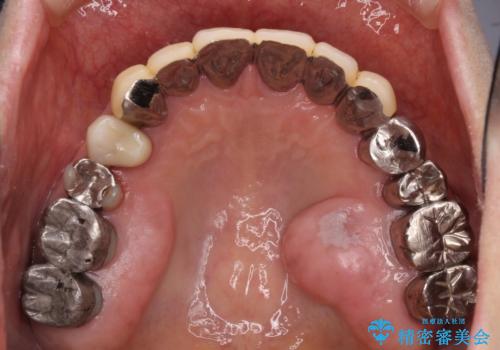

- 他院で抜歯が必要と診断され、インプラント治療を希望して来院された患者様です。

より審美的で、より機能的に優れた治療をご希望とのことであったので、ジルコニアカスタムアバットメントを用いたインプラント治療を行うこととしました。

ジルコニアカスタムアバットメントは、歯肉ラインに金属が見えにくいというだけでなく、クラウンを装着する土台の形が天然歯と近い形態となるため、清掃性が高く歯肉が腫れにくいというメリットがあります。

インプラントは、人工骨を用いた際の骨誘導能が比較的高いとさせるストローマン社のSLActiveを使用しました。